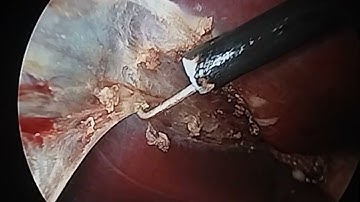

Hook dissection in laparoscopic cholecystectomy @drvikrantsinghchandail